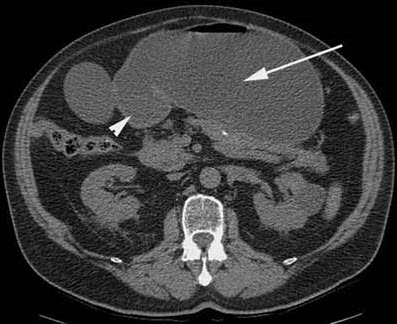

Diagnostic studies. A CT scan of the abdomen reveals a markedly dilated stomach with an obstructive mass in the descending portion of the duodenum; these findings are consistent with gastric outlet obstruction (Figure 2). In addition, biliary and pancreatic ductal dilatation and multiple liver masses are noted. Esophagoduodenoscopy shows near complete luminal obstruction by the mass (Figure 3). The scope is unable to pass beyond the markedly narrowed lumen. Results of biopsies of the duodenal mass reveal moderately differentiated invasive adenocarcinoma (Figure 4).